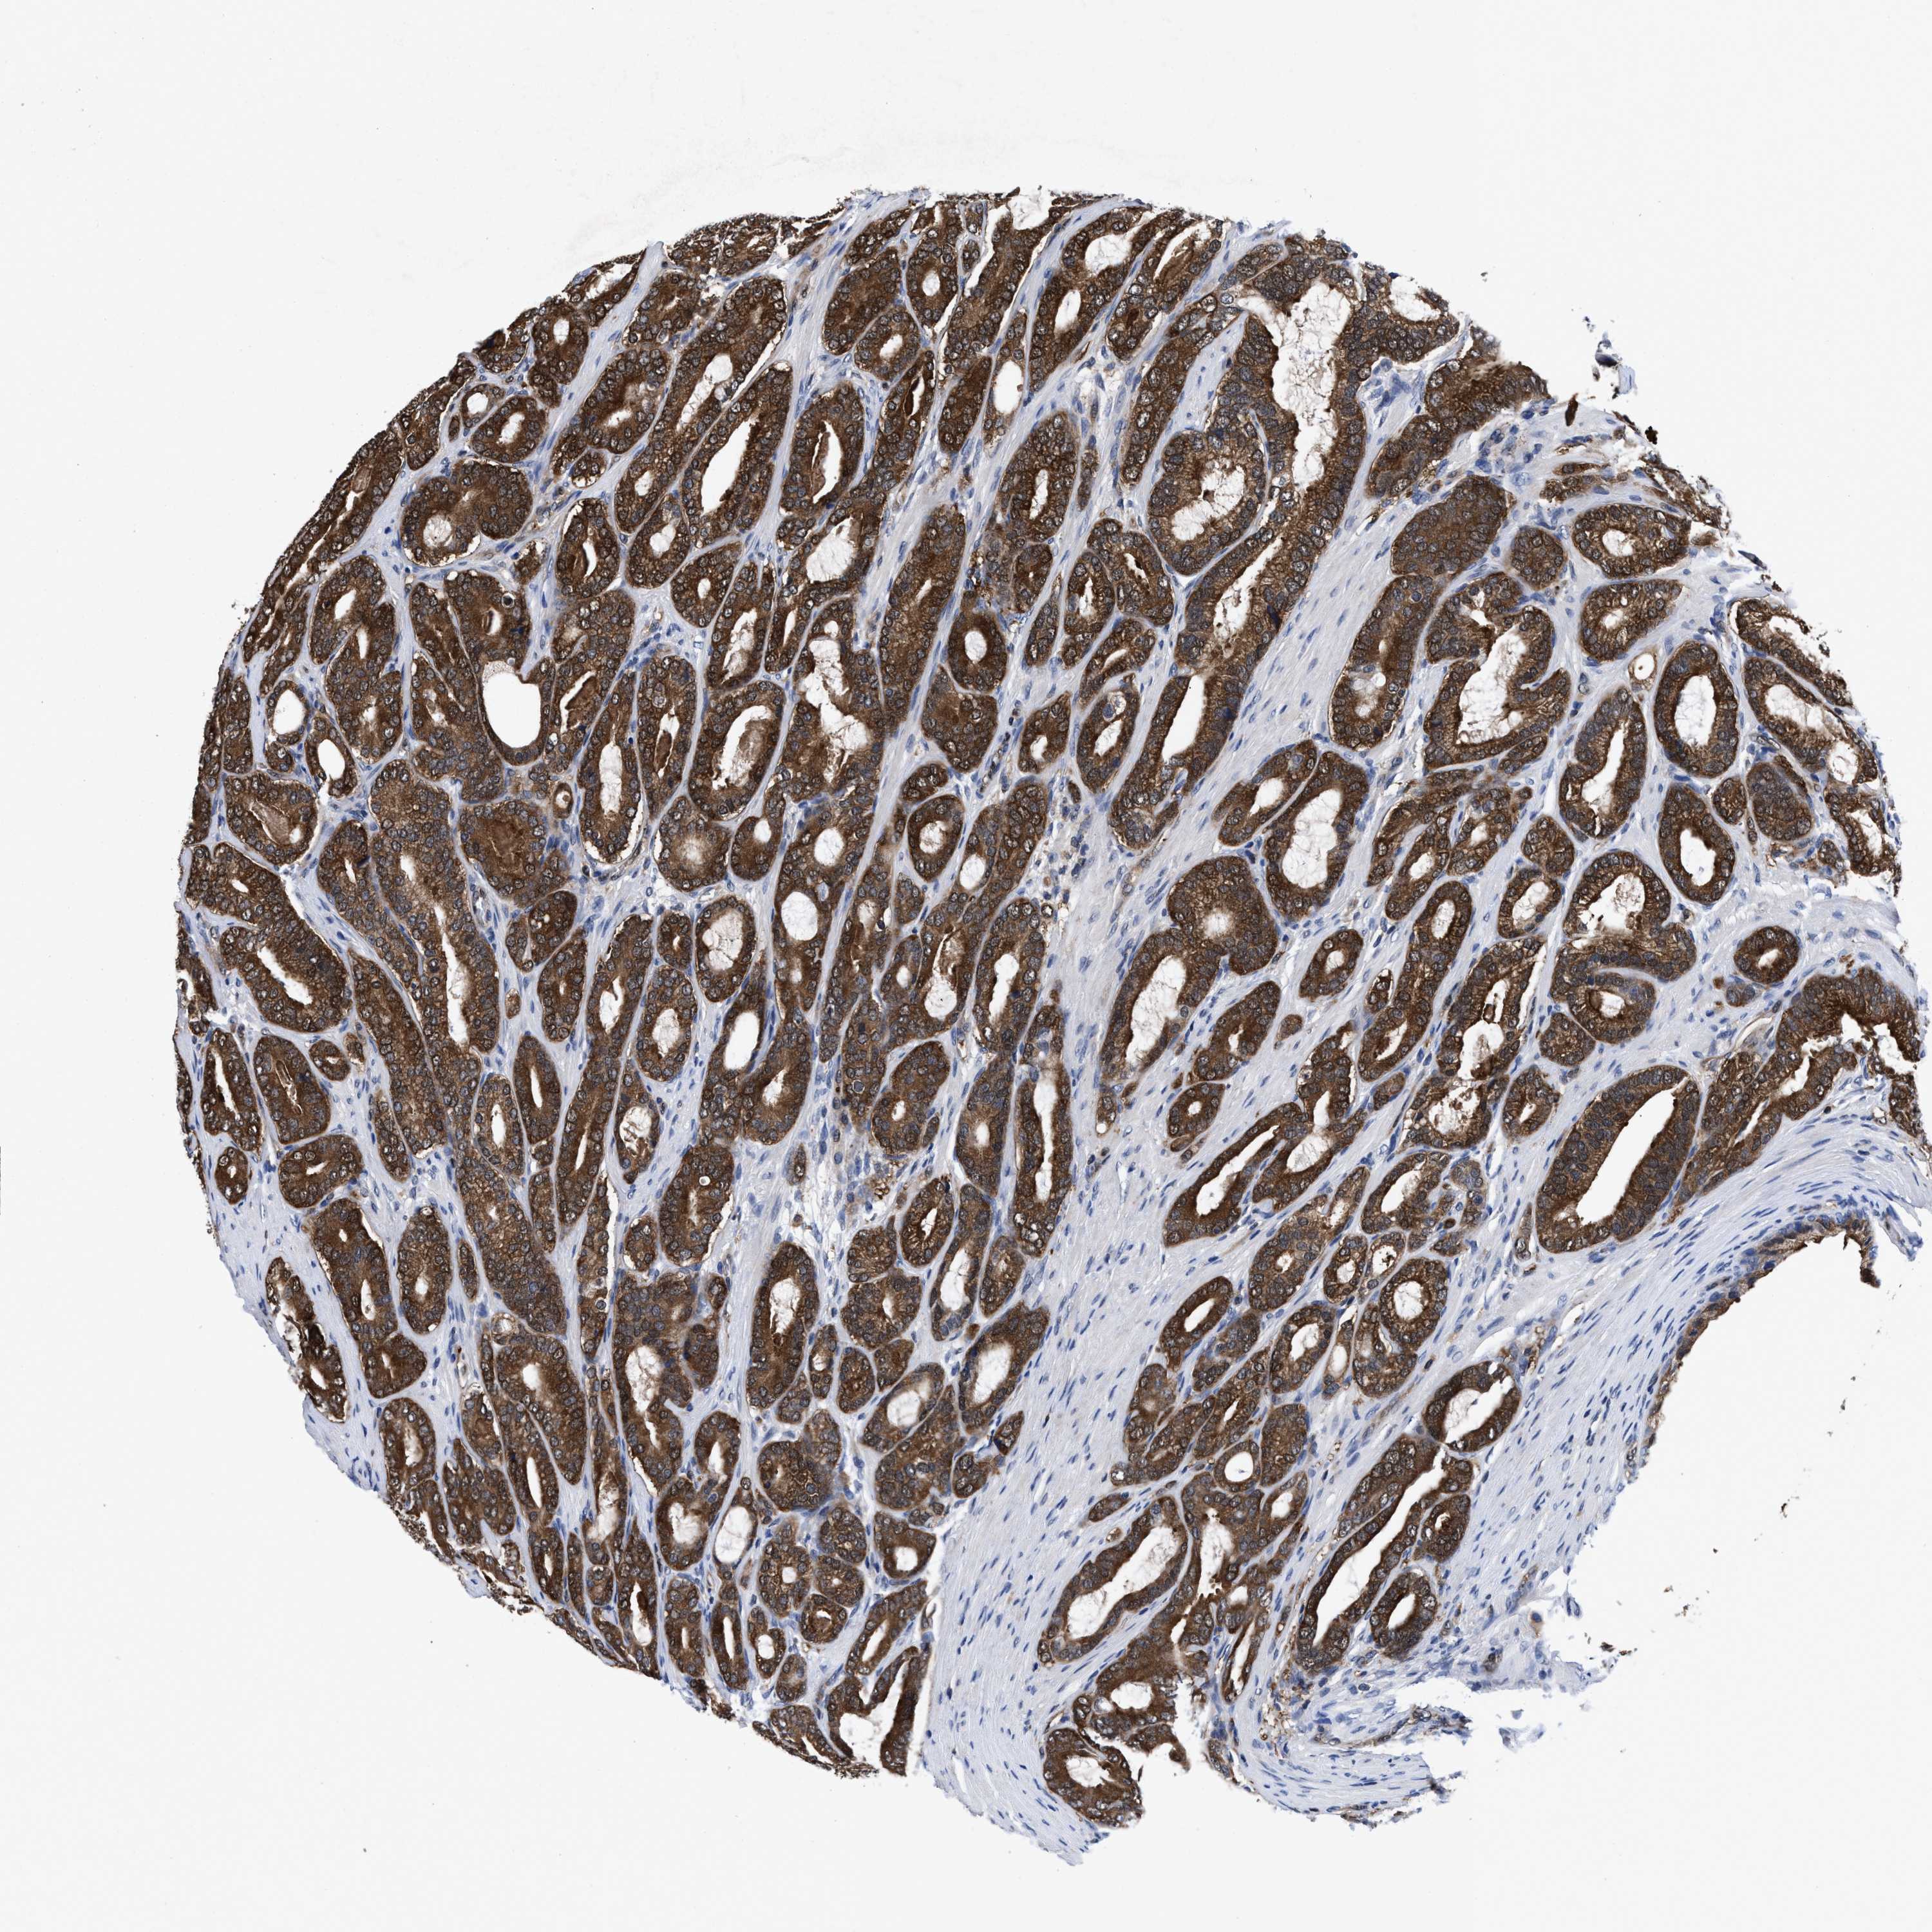

PROSTATE CANCER - Protein expressioni

A mouse-over function shows sample information and annotation data. Click on an image to view it in a full screen mode. Samples can be filtered based on level of antibody staining by selecting one or several of the following categories: high, medium, low and not detected. The assay and annotation is described here.

Antibody stainingi

Antibody staining in the annotated cell types in the current human tissue is reported as not detected, low, medium, or high, based on conventional immunohistochemistry profiling in selected tissues. This score is based on the combination of the staining intensity and fraction of stained cells.

Each image is clickable and will lead to virtual microscopy that enables deeper exploration of all samples and also displays staining intensity scores, fraction scores and subcellular localization as well as patient and tissue information for each sample.

HPA022434

HPA022953

HPA022959

HPA028758

CAB007783

Staining

High

Medium

Low

Not detected

Intensity

Strong

Moderate

Weak

Negative

Quantity

>75%

75%-25%

<25%

None

Location

Nuclear

Cytoplasmic/membranous

Cytoplasmic/membranous,nuclear

Adenocarcinoma, High grade

Adenocarcinoma, Low grade